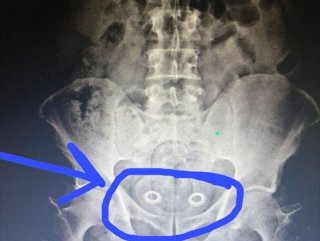

MİDE VE BAĞIRSAKLARINDAN ÇIKTI

Burada çekilen röntgen sonucu İran uyruklu A.P.'nin mide ve bağırsaklarında kapsüller içerisinde 107.92 gram metafetemin, folyoya sarılı 3 gram metamfetamin, 64 gram esrar tespit edildi. Gözaltına alınan İran uyruklu A.P. ile beraberindeki N.Ş., Ö.A., M.Y., Ş.K.'nin emniyetteki işlemleri sürüyor.